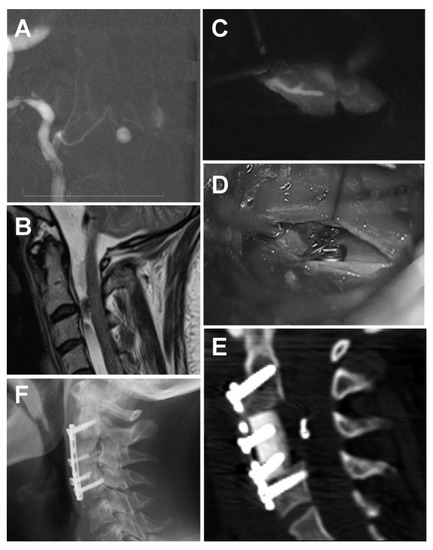

Spontaneous Subarachnoid Hemorrhage in a Patient with a Co-Existent Posterior Communicating Artery Aneurysm and Cervical Spine Aneurysm Associated with Ventral Arterio-Venous Fistula

2. Case Report